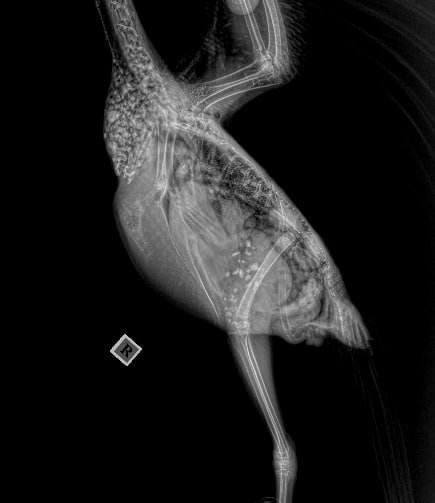

Svetlya4ok Опубликовано 3 декабря, 2025 #1 Опубликовано 3 декабря, 2025 Добрый день! Нашла птенца, неделю жил у меня, кормила кашей, после того как начал самостоятельно есть зерно, стал хохлиться, вялый, и появилась рвота. Пошли к веторнитологу, слелали рентген , прослушали и назначили лечение. Лекарства ,кот назначил врач давала 3 дня и кормила нутриберд а 21 .птице стало хуже, перестал есть сам, зоб стал. Отменила все лекарства. Дала атоксил, грела птицу, массировала зоб, дала кальция глюконат 0.2 мл в клюв, чтобы запустить перельстатику. Ночью все вырвал,зеленая рвота и зерна непереваренные 3х дневной давности. Очень похудел. После рвоты дала еще атоксил, и потом перешли на детскую безмолочную кашу без сахара, еда стала уходить🙏+ добавила флуконазол 50 мг ( капсула в 5 мл воды в клюв 0.2) вес птицы 195 гр. птица попрежнему вялая, все время сидит на грелке. Как помочь еще я могу

rina-maxus Опубликовано 3 декабря, 2025 #2 Опубликовано 3 декабря, 2025 (изменено) @Svetlya4ok чтобы сейчас не терять время, напишите @Zosia в ВА, скинув рентген и назначения и описав ситуацию.Контакты указаны в профиле. Скрин ниже.❤️ @маленький принц Изменено 3 декабря, 2025 пользователем rina-maxus 1